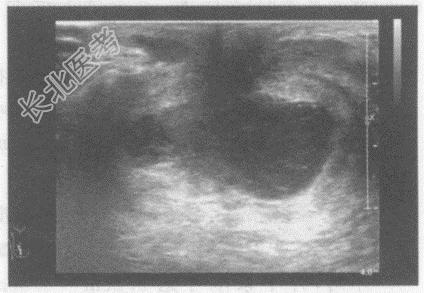

- 单项选择题临床资料:女, 29岁,哺乳期, 自述右乳房肿痛1周。

临床物理检查:右乳房红、肿、热、痛, 体温38.5℃。

超声综合描述:右乳头后方可见低回声区, 形态不规则,边界显示不清, 内可见不规则无回声区,无回声区内可见中强回声光点浮动, 探头加压局部疼痛明显,CDFI: 周边可见散在点状动静脉血流信号。见下图及彩图。

超声提示: A、急性乳腺炎合并乳腺脓肿